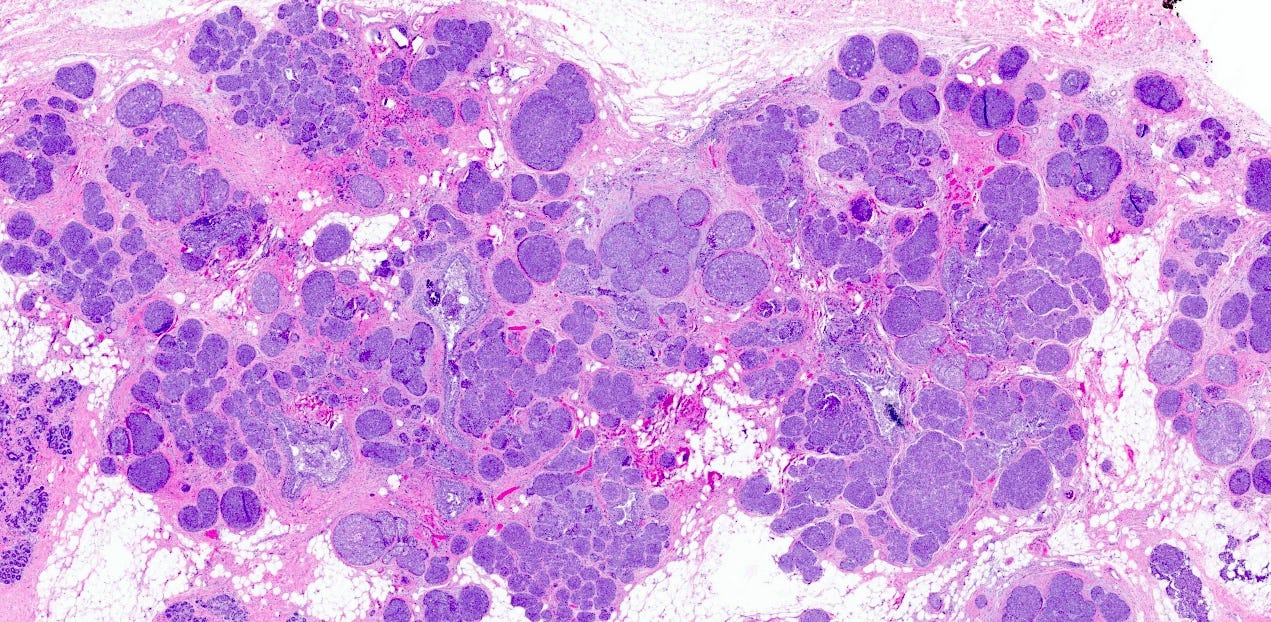

Classic LCIS - microscopic images

As shown below, LCIS is characterized by a lobulocentric proliferation of cells that expand lobular units. The LCIS cells are uniform, loosely cohesive and evenly spaced (“marbles in a bag”). They are slightly larger than normal breast epithelial cells, with indistinct cell borders and pale cytoplasm. Two types may coexist. Type A LCIS cells have small to slightly enlarged, uniform, round nuclei with inconspicuous nucleoli. Type B cells have larger nuclei, more abundant cytoplasm and more prominent nucleoli.

Classic LCIS is usually an incidental finding in a breast biopsy performed for other indications, including screening detected calcifications or mass producing lesions. The calcifications are frequently produced by columnar cell lesions, a low risk lesion. LCIS lesions are frequently found as multiple foci within the same (70%) or both breasts (20 - 60%).

LCIS is a risk factor for subsequent breast cancer: women with LCIS have a 7 - 10 fold increase in breast cancer risk, an absolute risk of 1 - 2% per year and a lifetime risk of 30 - 40%. The time from LCIS diagnosis to cancer ranges from 15 to 30 years.

Classic LCIS is typically treated conservatively with active surveillance and anti estrogens. Unlike DCIS, it is no longer considered a malignant condition. If diagnosed incidentally, excision is not recommended because the risk of finding invasive carcinoma on excision is very low (< 5%). Excision is recommended only if other high risk proliferative lesions are found or there is discordance between histology and imaging (i.e. the microscopic findings are different from what is expected from the imaging, suggesting the lesion was missed).